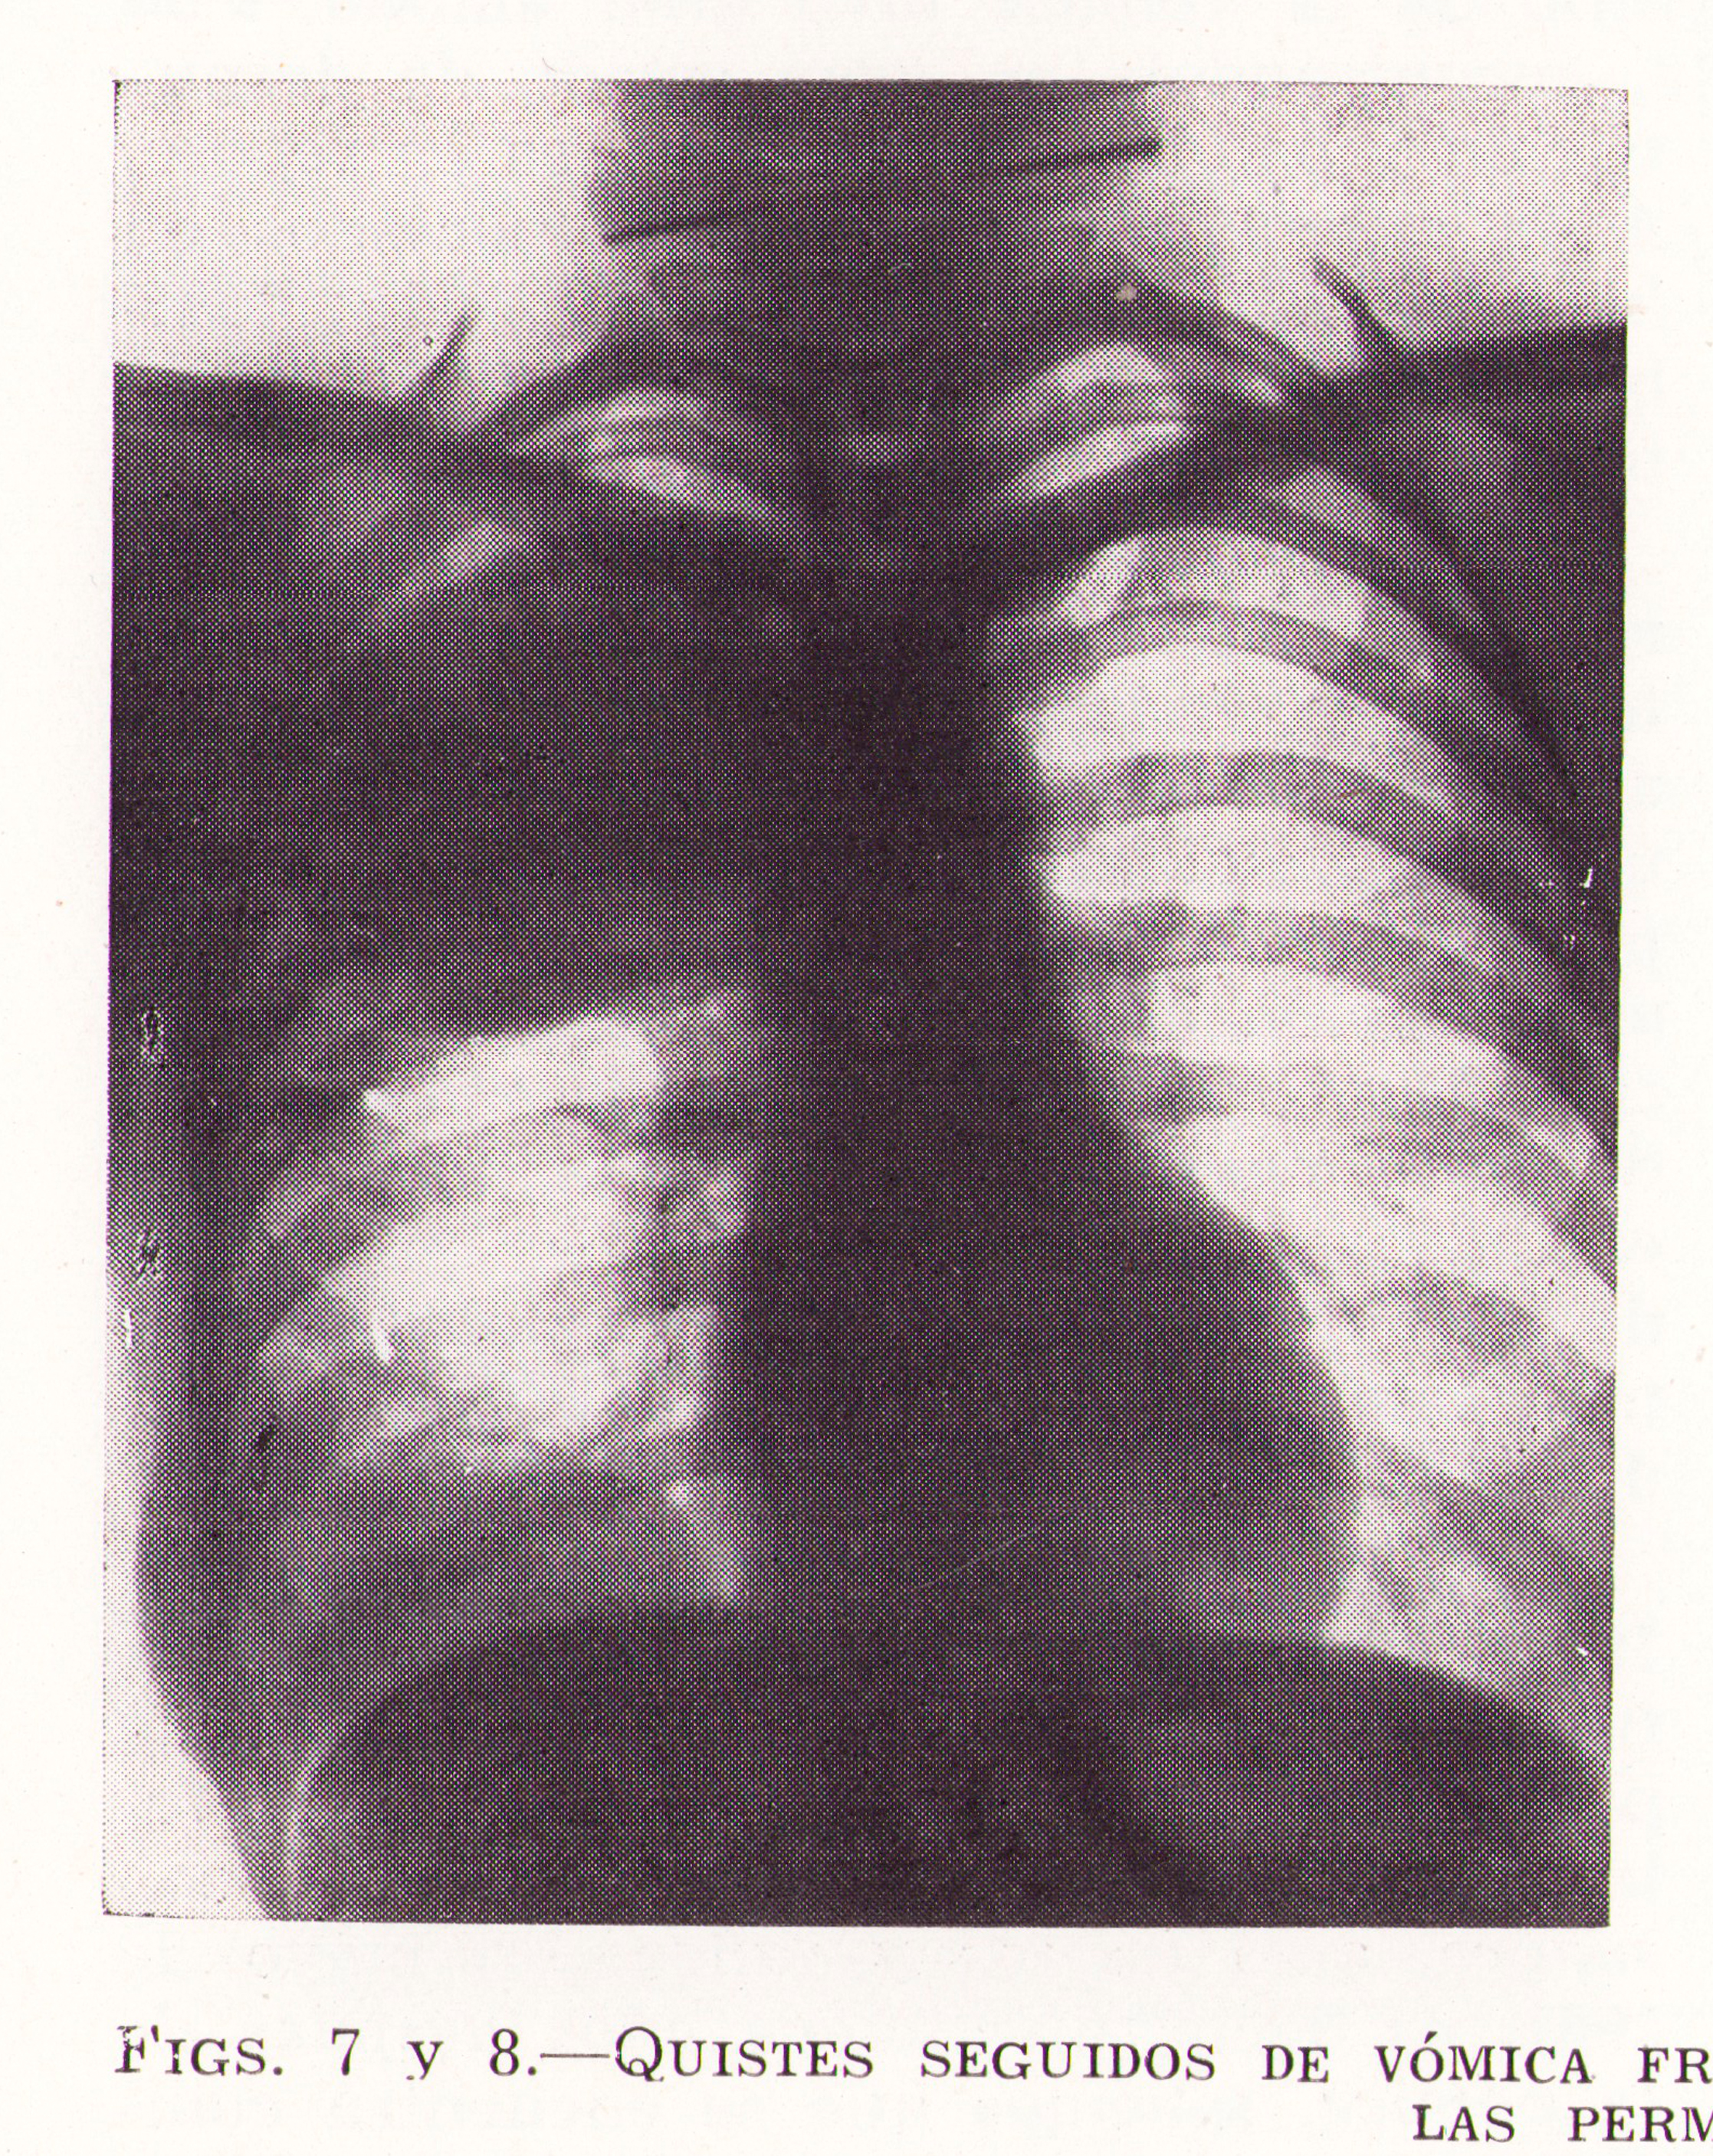

Quistes seguidos de vómica fraccionada con secuelas

Fig.7. Revista Española de ciencias médicas, Clínica y laboratorio, 1953.